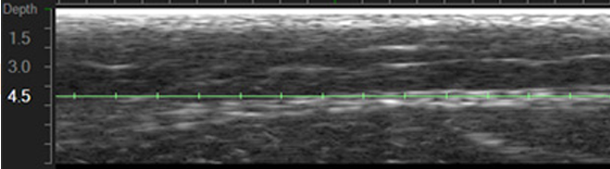

직접 울쎄라에 나오는 초음파 영상을 잠시 보여드리면

4.5mm 팁을 사용한 영상입니다.

초록색 선이 실제로 초음파가 작용을 하는 깊이가 되고

그 주변으로 보이는 하얀색이 근막층이 됩니다.

따라서 위 초음파영상은 정확한 층에 제대로된 팁을 사용한 모습입니다.